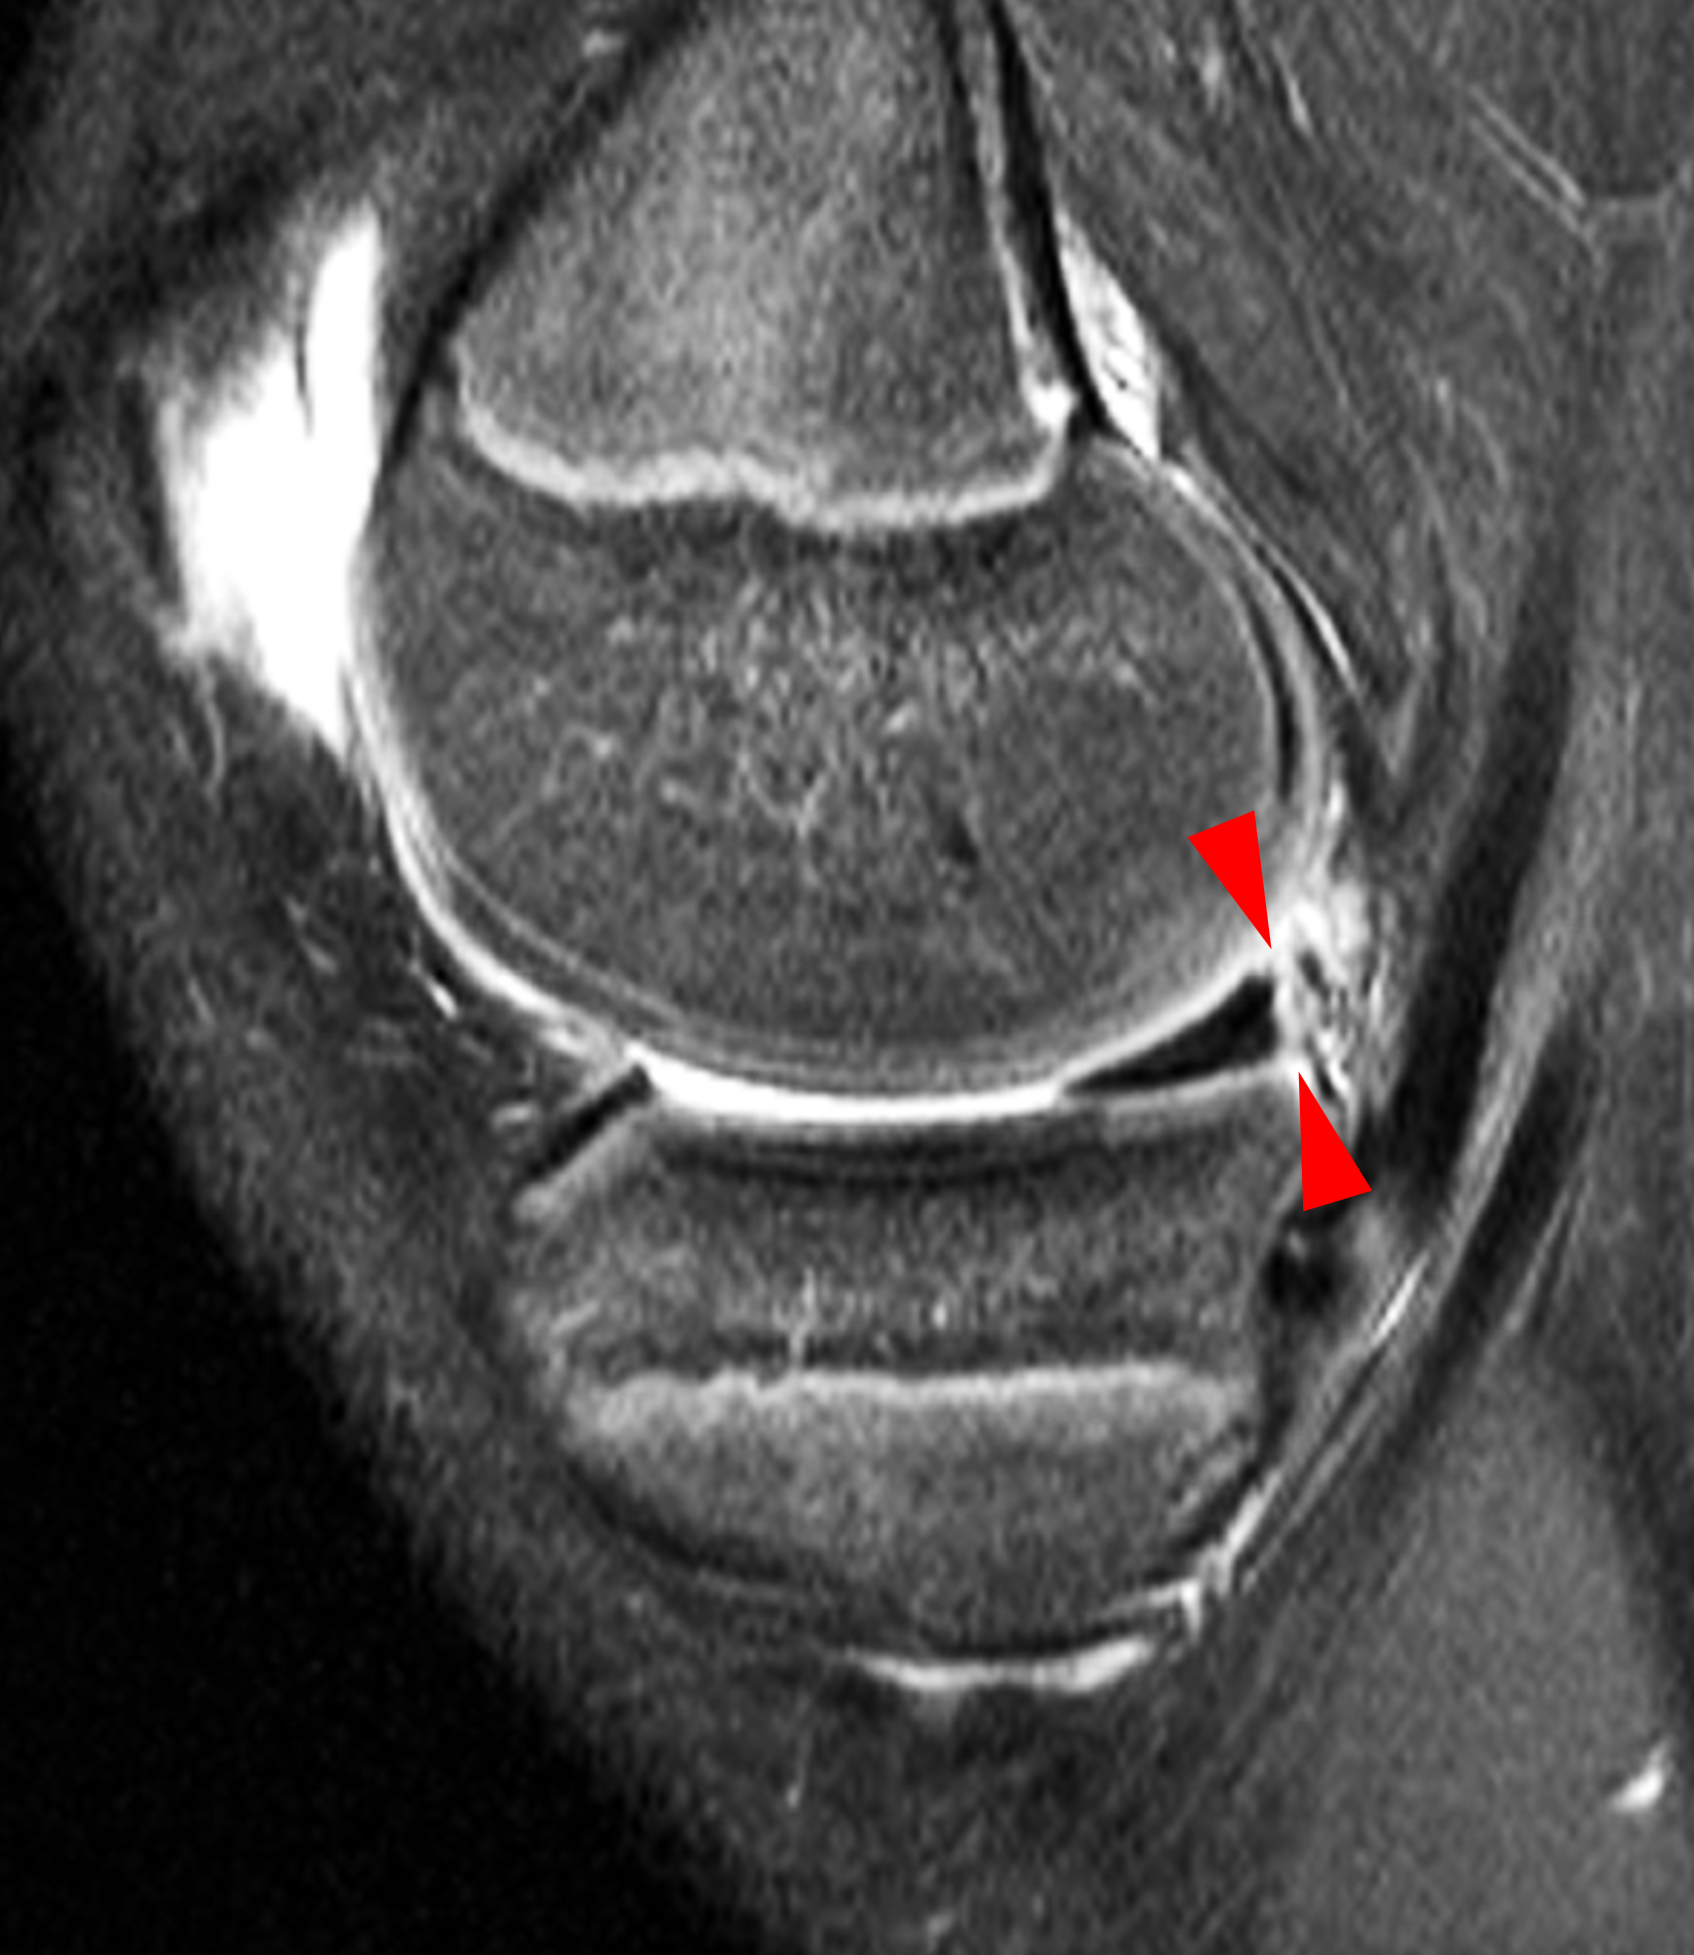

A 19-year-old collegiate baseball player sustained a twisting injury to the knee 3 weeks earlier. Sagittal (1A) proton density-weighted fat-suppressed image through the intercondylar notch, (1B and 1C) proton density-weighted images through the medial compartment, and (1D) fat-suppressed proton density image through the medial compartment are provided. What are the findings? What is your diagnosis?

Figure 2: (2A) Sagittal image through the intercondylar notch shows a complete tear of the anterior cruciate ligament (arrowheads). (2B and 2C) Near the posterior meniscocapsular junction of the medial meniscus, there is disruption of the posterior meniscotibial ligament (red arrow) and irregularity of the posterior meniscocapsular ligament (yellow arrow). (2D) On the fluid-sensitive sequence, linear high signal intensity is interposed between the ligaments and the posterior horn of the medial meniscus (arrowheads).

Anterior cruciate ligament tear with a medial meniscal ramp lesion.